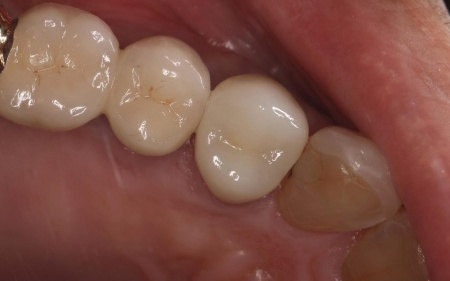

| 行ったご提案・治療内容 | 診断結果を丁寧に説明したうえで、古い被せ物を外し歯に合った新しい被せ物を作製する治療を提案し、同意いただきました。

この歯は過去の治療で被せ物を装着する際に歯の神経を取る根管治療を行っていました。 患者様は「見た目がきれいで長持ちする被せ物がいい」と希望され、被せ物の種類は自由診療のセラミックであるジルコニアクラウンを選択しています。 ジルコニアクラウンのメリット・デメリット まず古い被せ物を除去して土台の形を整え、精密な型取りを行いました。 |

治療後